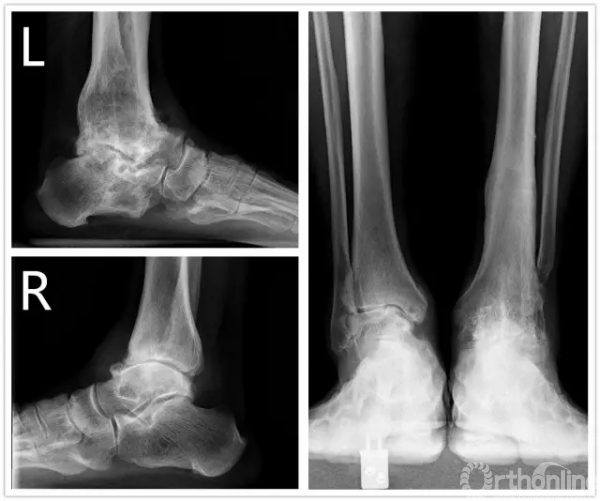

方老伯,今年67岁,20067月他因左侧踝关节严重骨关节炎到上海瑞金医院就诊,当时刘津浩副主任考虑其踝关节和距下关节都已经出现严重的骨关节炎,无法保留关节,于是对其进行了胫距跟双关节融合手术。手术后方老伯恢复良好,如期达到骨性融合。2年后,方老伯右侧踝关节开始出现肿胀疼痛,日夜反复发作,直到20102月,他无法忍受,再来医院就诊,拍片后发现他右侧踝关节也出现明显骨关节炎。此时正值瑞金医院足踝外科全面发展时期,足踝外科的新理念、新技术已经引入瑞金医院,当时学科带头人徐向阳主任认为该患者左侧踝关节已经行融合手术,右侧不适宜再行融合手术。于是徐主任主刀、刘津浩副主任和朱渊医师担任助手,顺利为方老伯进行了踝关节STAR假体置换术,手术后保持随访康复良好,又恢复了往常的劳作。

直到1年前,方老伯感觉右侧踝关节又开始出现肿胀疼痛,劳作后加重,最近越来越重。20167月再来徐主任门诊复查,徐主任考虑踝关节假体出现了松动,距骨有了塌陷,关节力线有所偏移。鉴于目前瑞金医院足踝外科已经开展踝关节INBONE假体置换术,积累了一定的经验,于是徐主任向患者及家属解释病情,建议再行踝关节翻修术。